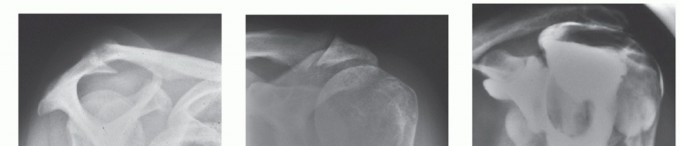

DEFINITION Proximal humerus fractures are defined as those of the proximal portion of the humerus involving t…